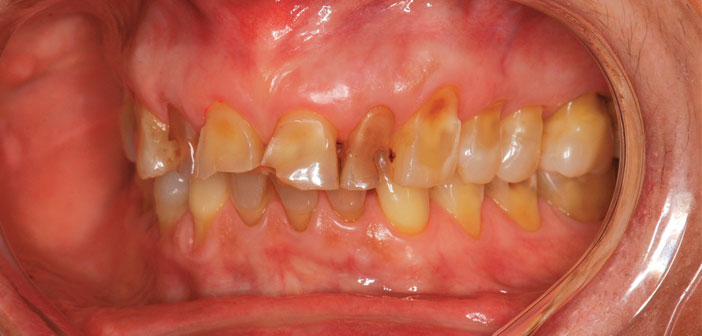

| Il existe plusieurs formes d’usure dentaire (chimique, fonctionnelle, parafonctionnelle…) et chacune d’entre elles présente un tableau clinique spécifique. Nous associons souvent usure et bruxisme, pourtant ce dernier ne concerne qu’un faible pourcentage de patients atteints d’usure alors que l’usure dentaire est très fréquemment visible dans la bouche de nos patients. |

| Ces dernières années, l’évolution du collage a permis l’optimisation des traitements minimalement invasifs. Parfaitement adaptés aux attentes et aux besoins des patients présentant des usures, le collage permet la restauration d’une dent à la réhabilitation globale « full mouth ». |

| Le patient âgé de 57 ans est demandeur d’une solution globale pour réhabiliter sa bouche. Pour élaborer le plan de traitement, nous suivons toujours le même chemin : discussion avec le patient pour connaître ses souhaits, désirs, limites en termes de traitement planification esthétique en utilisant l’outil Digital Smile Design (DSD) |